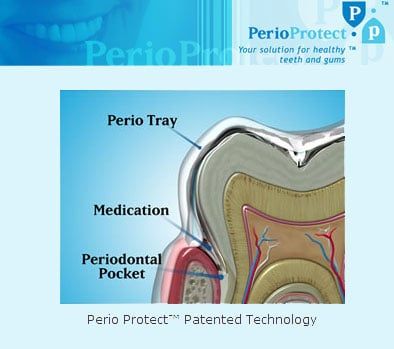

Perio Protect

The custom perio tray is fabricated to fit precisely over your teeth and gum tissue. The special seal helps to place medications into the gingival crevice or periodontal pocket. Your dentist will determine what medication is most appropriate for your perio treatment needs and how often to wear the perio tray. It is convenient, comfortable, and easy to use.